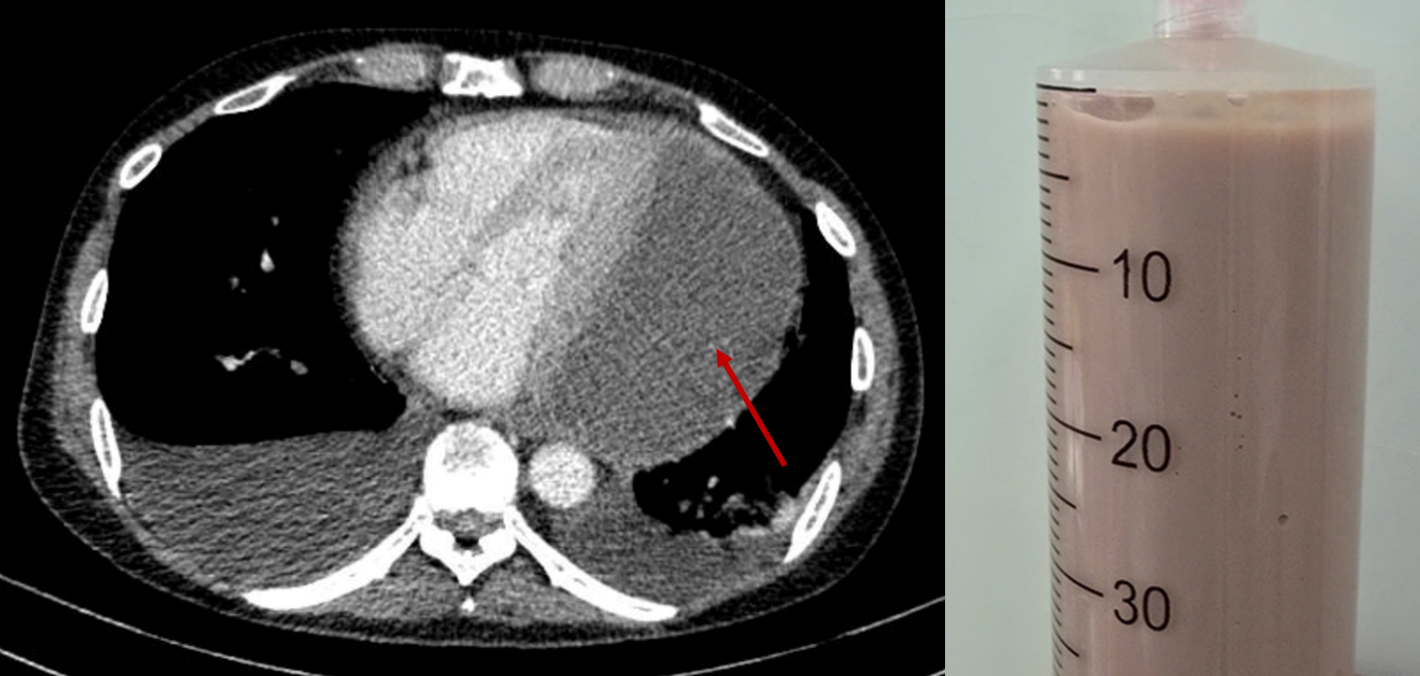

Khi đến Bệnh viện Nhân dân 115, người bệnh trong tình trạng suy kiệt toàn thân, phải thở oxy liều cao, huyết áp tụt và mạch rất nhanh, phù toàn thân. Qua siêu âm các bác sĩ phát hiện một khối dịch lớn gần 11cm bao quanh tim – nguyên nhân khiến tim bị ép chặt, co bóp khó khăn và đe dọa tính mạng người bệnh từng giây.

Ngay lập tức, các bác sĩ từ nhiều chuyên khoa đã cùng nhau thảo luận và quyết định can thiệp chọc hút dịch mủ ra khỏi màng ngoài tim khẩn cấp. Đây là một ca chọc hút không đơn giản và tiềm ẩn nhiều nguy cơ do khối mủ nằm ở vị trí khó tiếp cận, dịch đặc quánh.

Với sự hỗ trợ của thiết bị siêu âm hiện đại tại giường bệnh, các bác sĩ đã hút thành công 500ml mủ đặc, giảm nhanh áp lực lên tim. Bệnh nhân được phẫu thuật mở cửa sổ màng tim để tiếp tục dẫn lưu toàn bộ dịch mủ còn lại. Đồng thời điều trị tích cực bằng kháng sinh mạnh, điều trị bệnh nền chặt chẽ, nâng thể trạng...